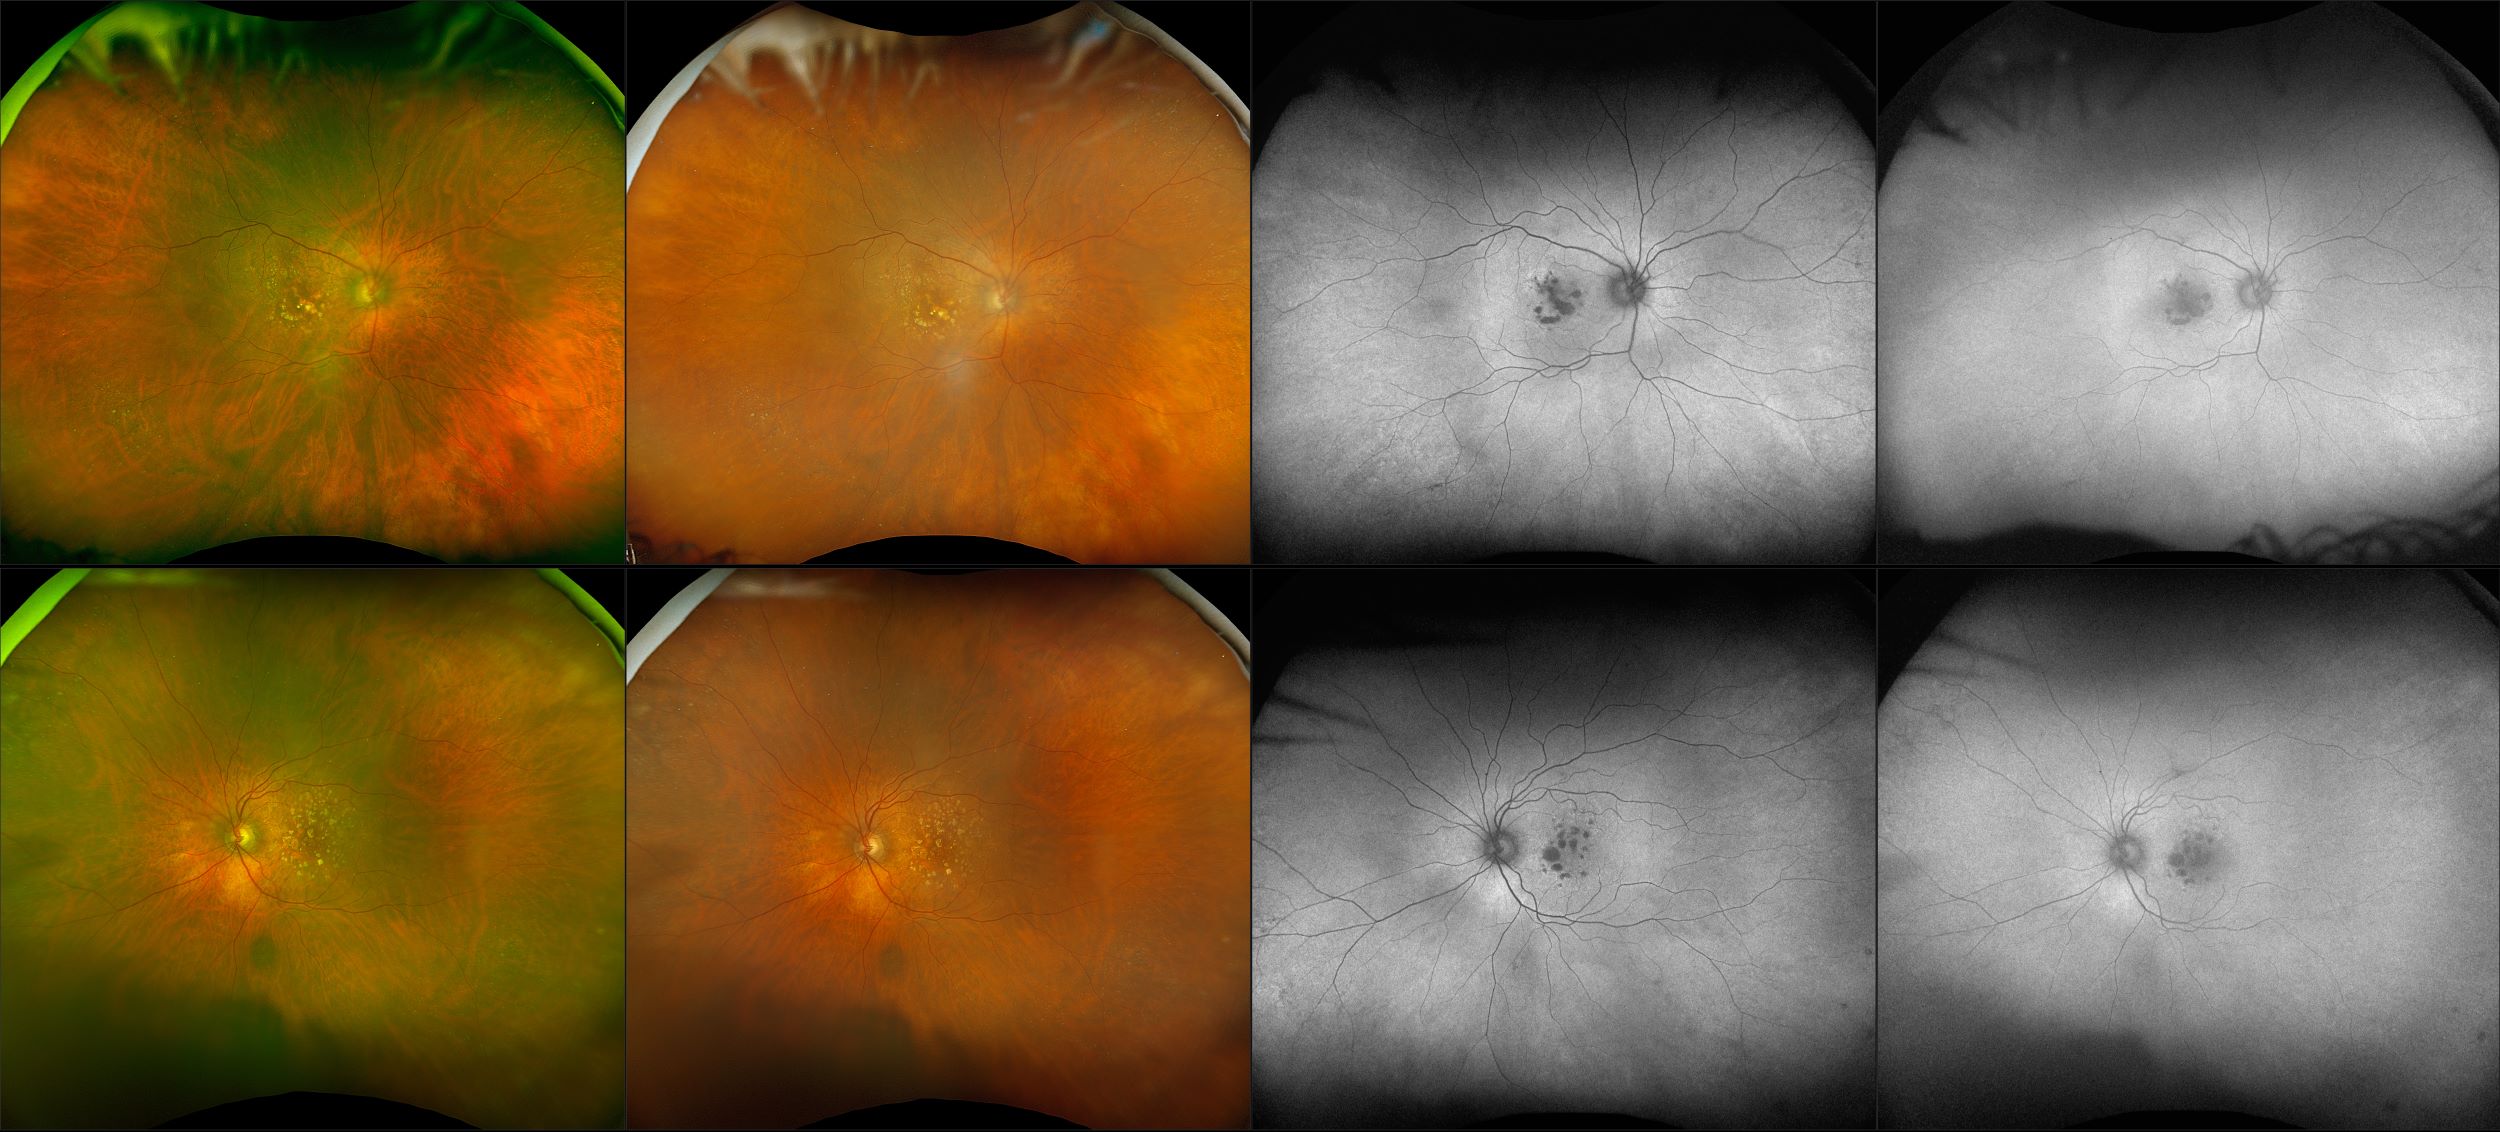

California - AMD, RG, AF

Age-related macular degeneration is found in two forms 1. Dry early form. 2. Wet (serous leakage or whole blood). Early dry form typically has drusen (usually around 63u) and RPE degeneration and only needs periodic follow-ups, intermediate dry form has large drusen (>125u) and RPE degeneration and proliferation which requires examinations every 3 to 6 months depending on the severity of the presentation.